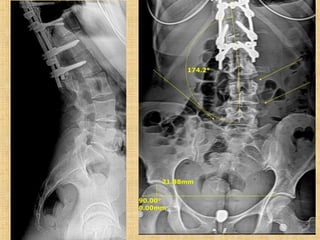

Linda 68 yo

Scoliosis / Unstable pelvis / Loss of foot dorsiflexion / Diffuse pain

9 months post

Linda 68 yo Scoliosis/ Unstable pelvis / Loss of foot dorsiflexion / Diffuse pain 9 months post

Scoliosis Patients Are Missinglateral Lordotic Curves…“Linda”